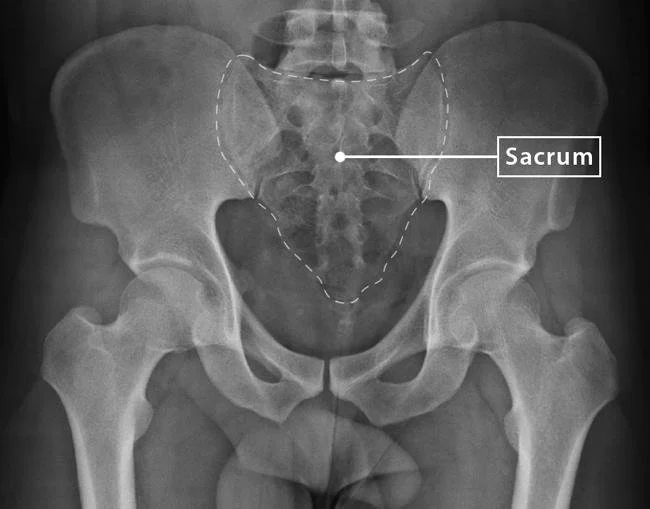

What Is the Sacrum?

The sacrum is that triangular bone at the base of your spine, nestled between the two sides of your pelvis. It’s not just a connector—it’s a shock absorber, movement regulator, and fascial anchor.